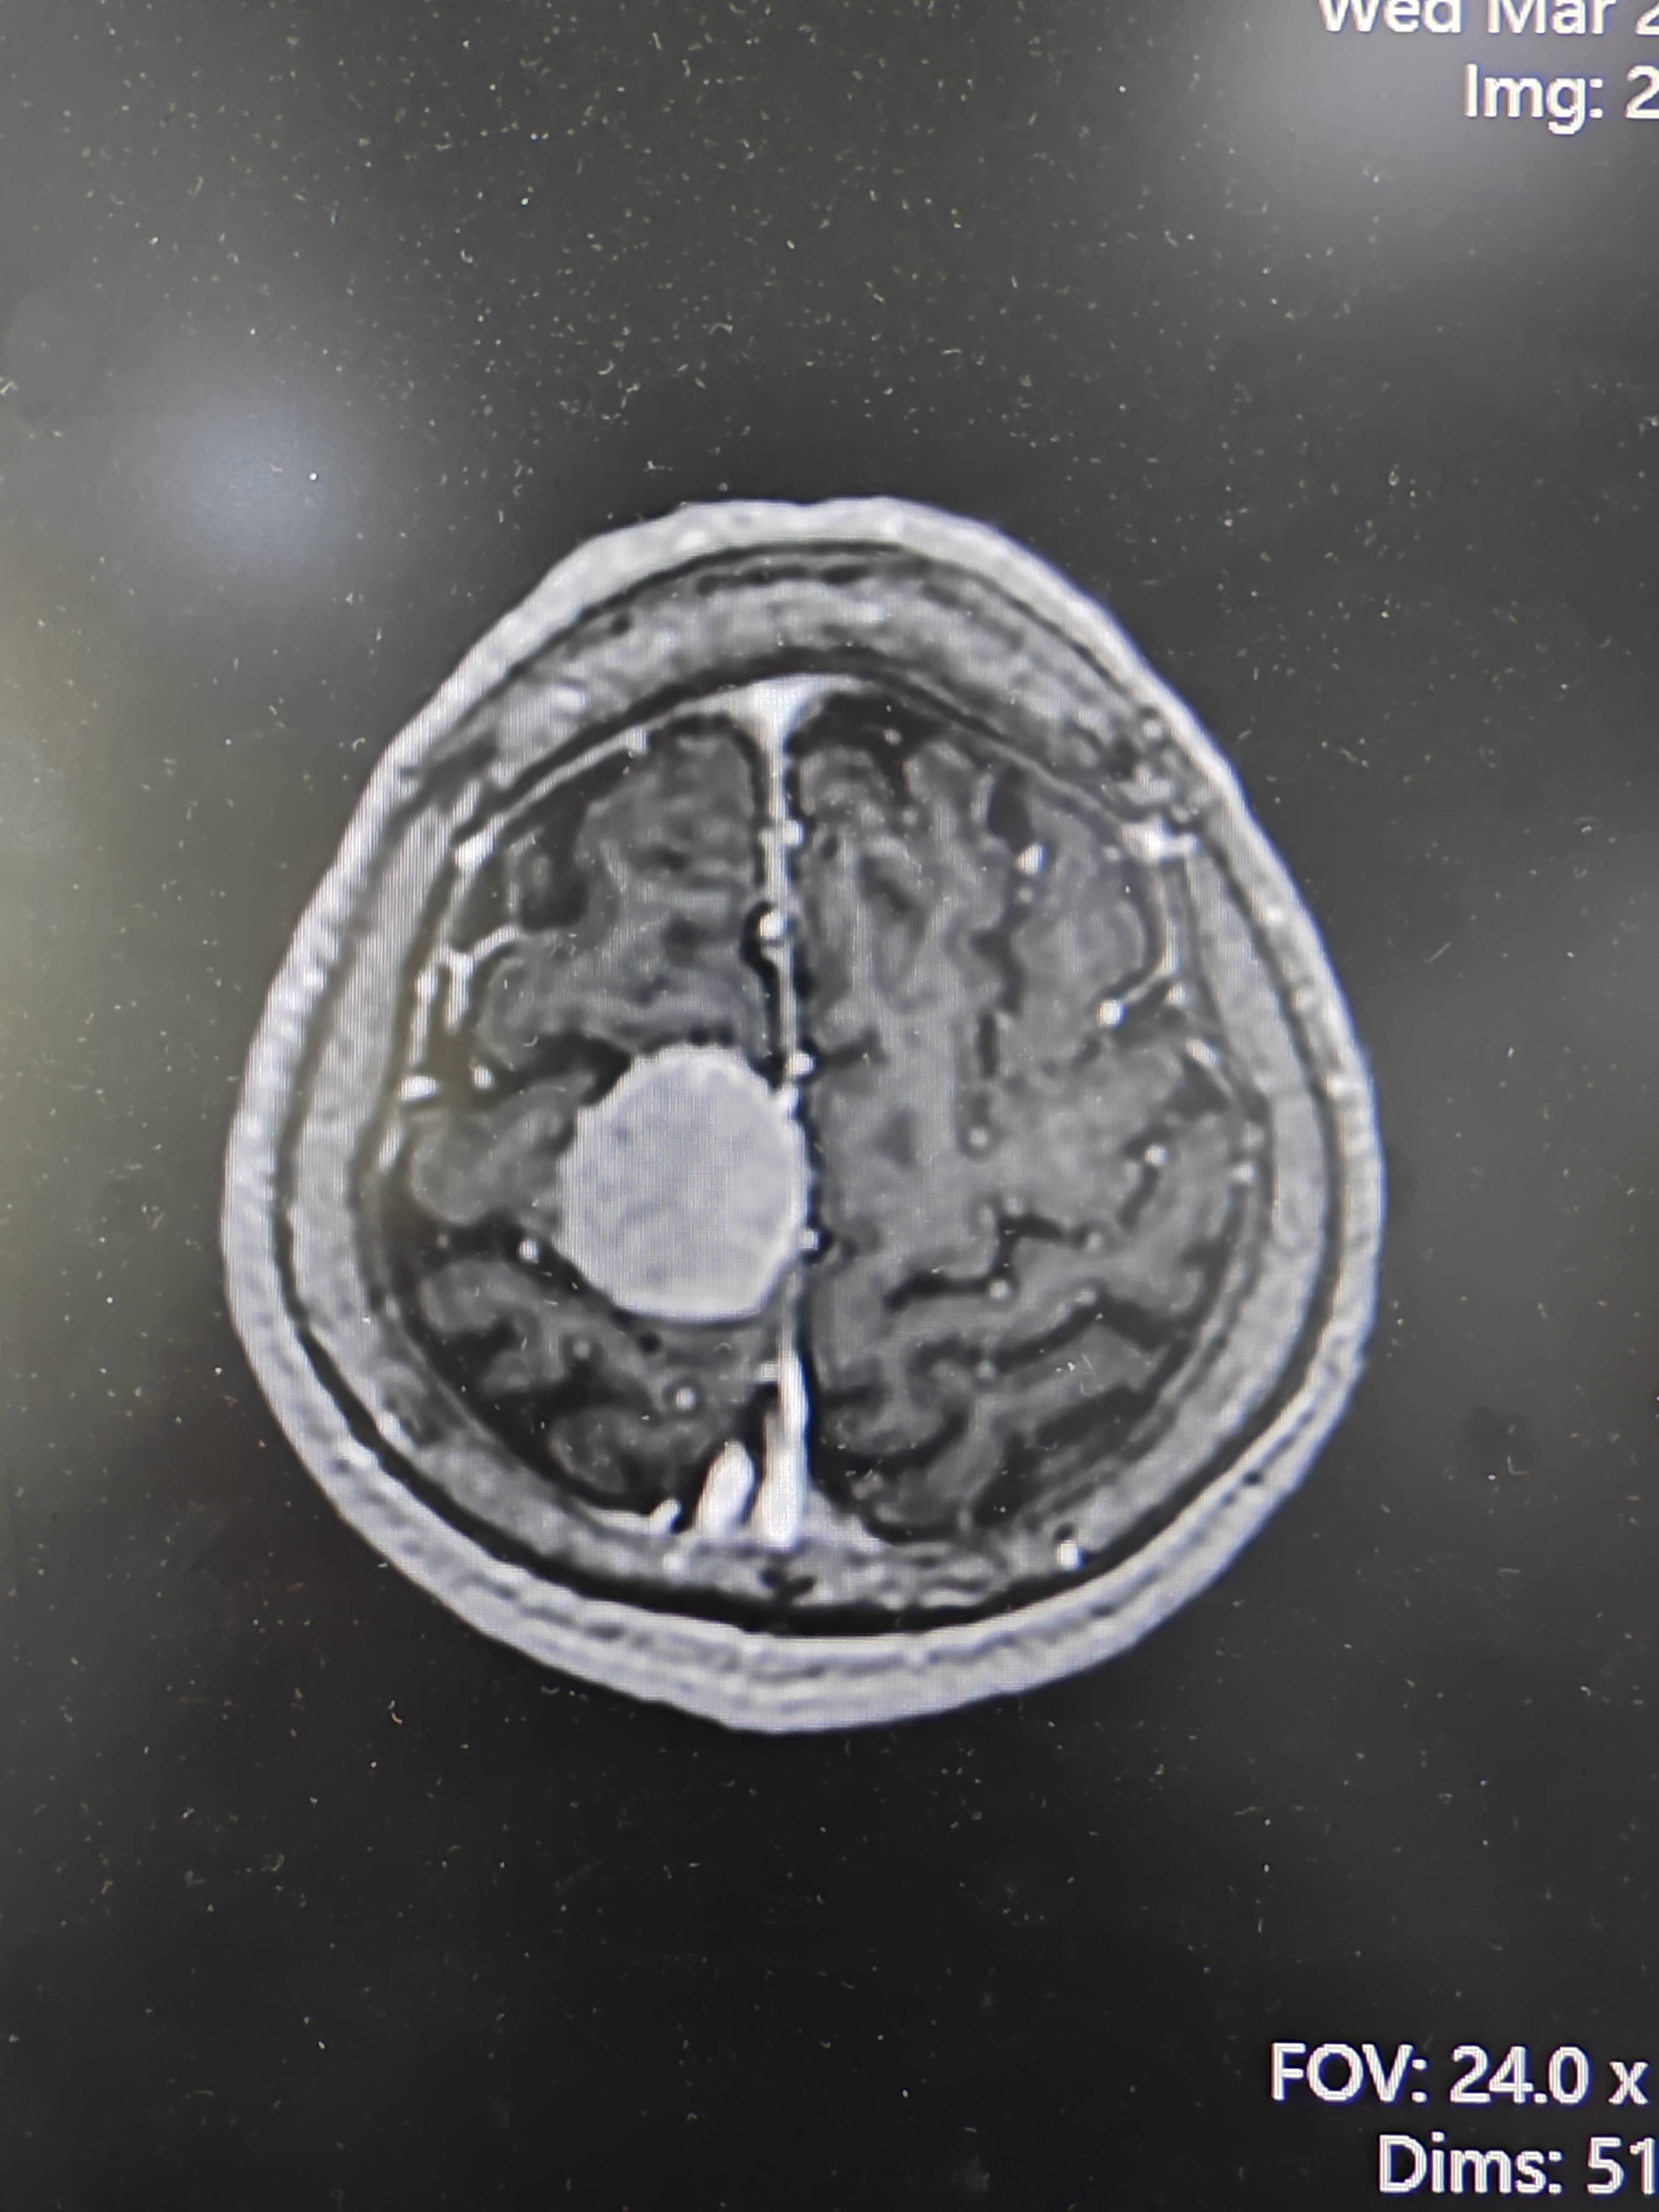

脑膜瘤,够典型吗? [病例帖]